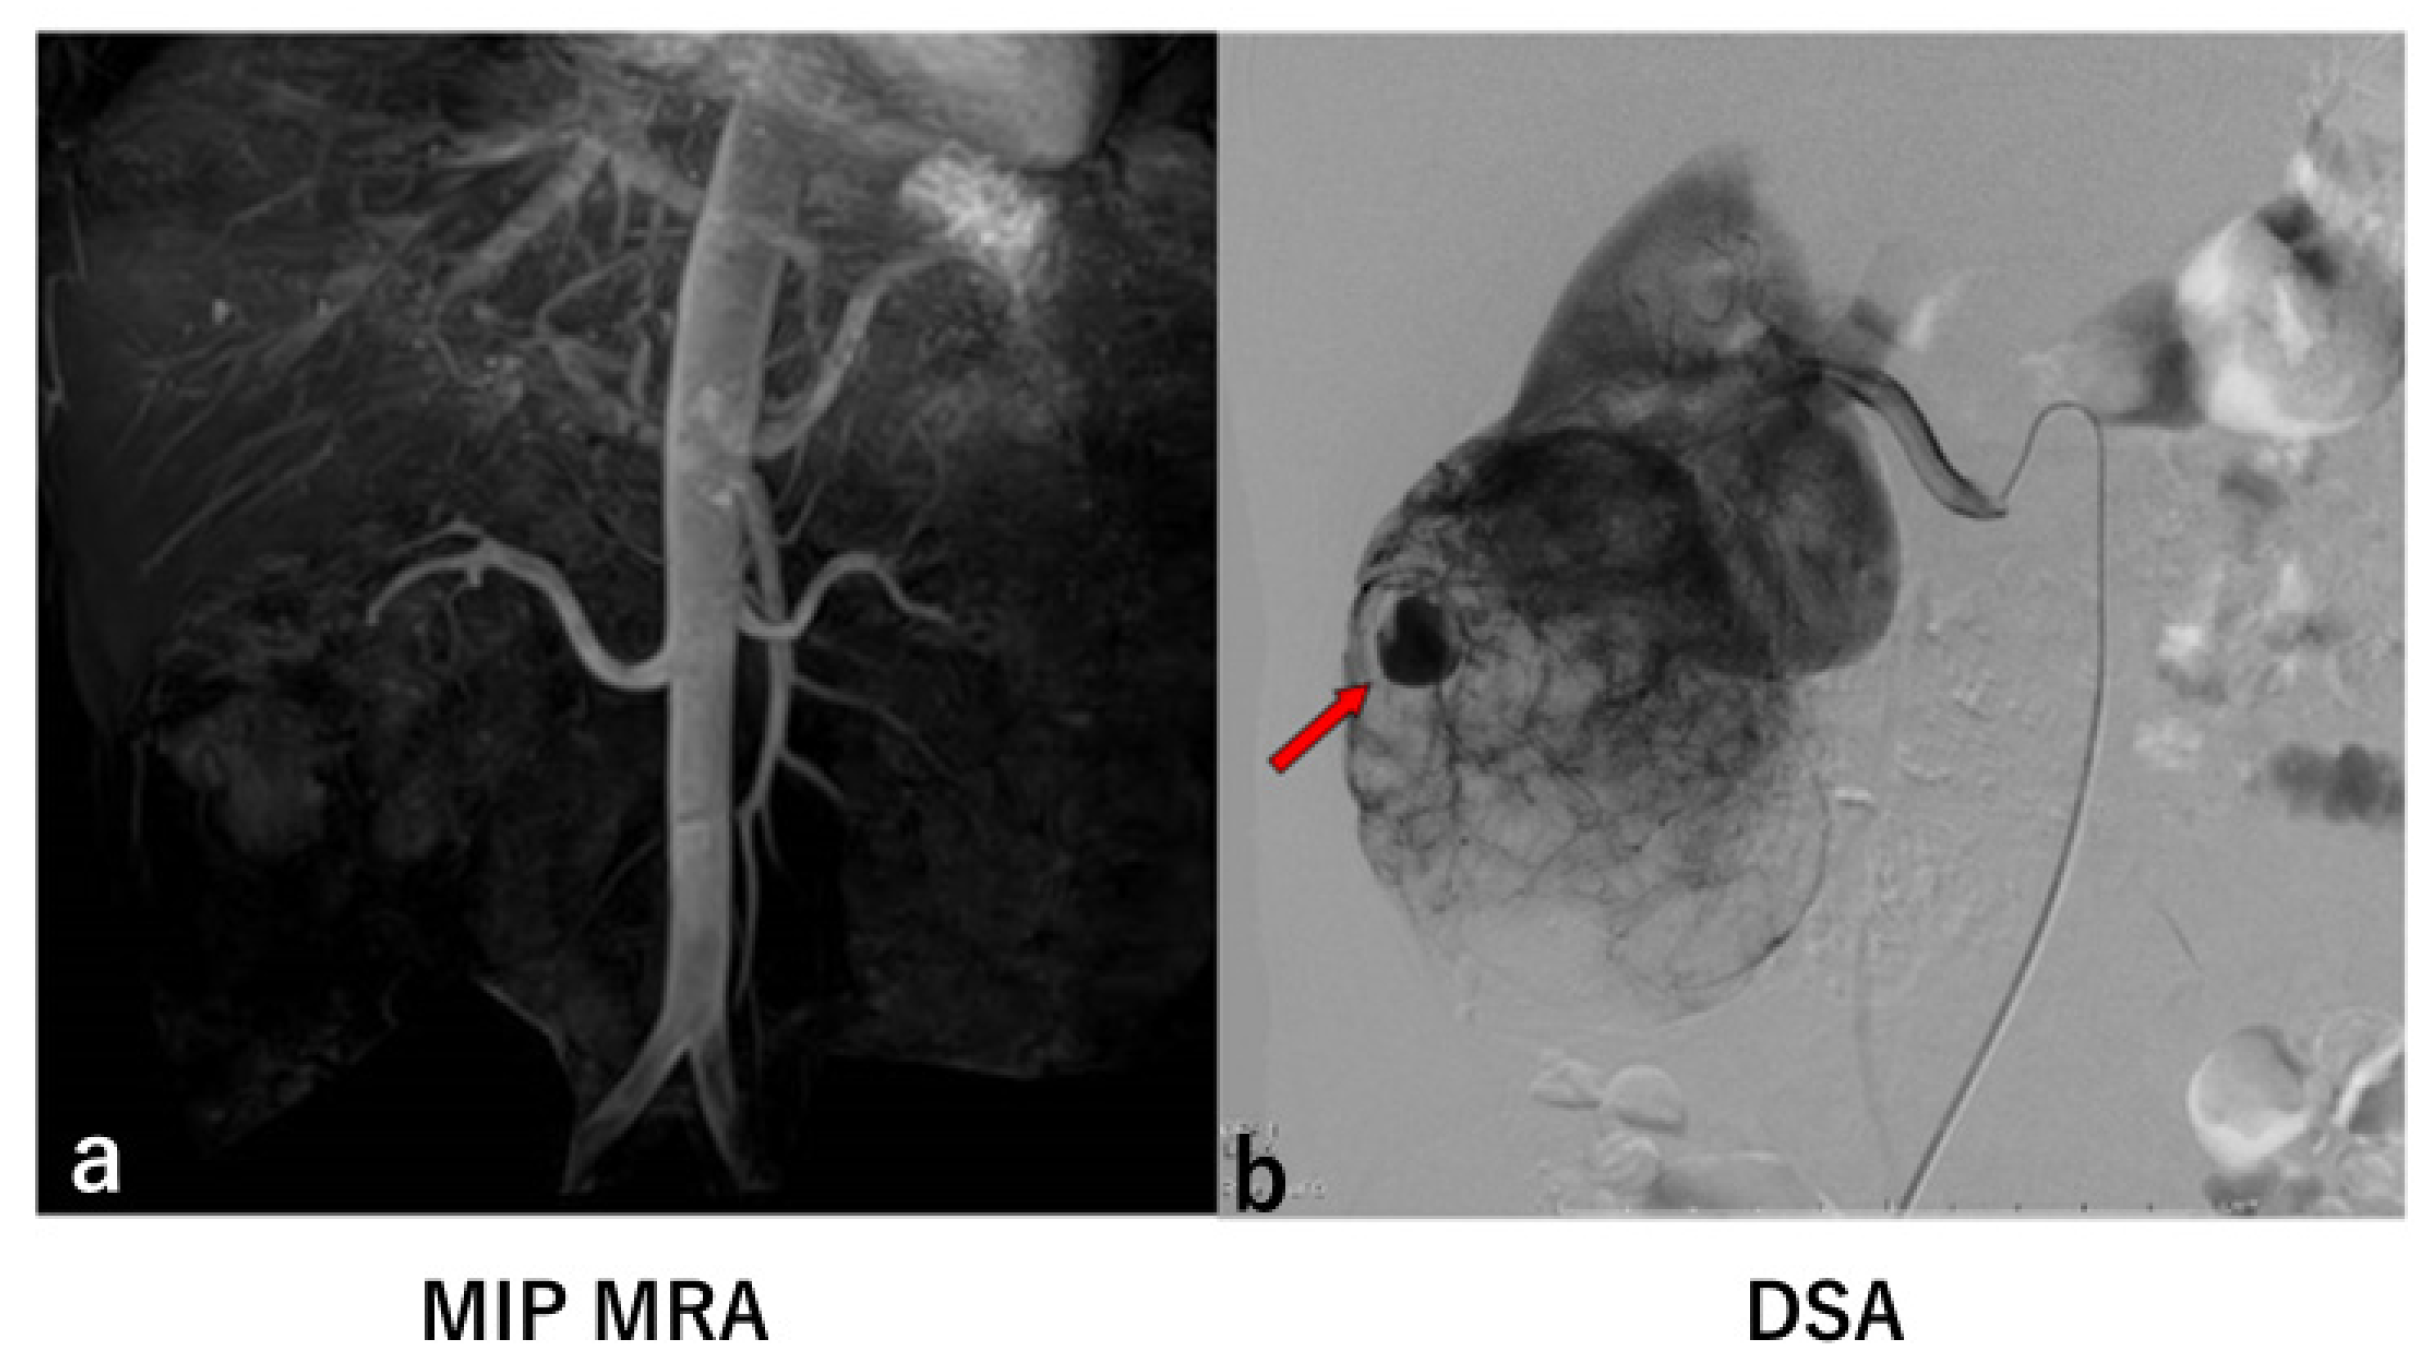

Introduction to Two False Negative Cases

| 7 | 50/F | sAML | Right | 0/1 (14 × 13 mm) | N/A *1 | 105 × 91 × 77 mm |